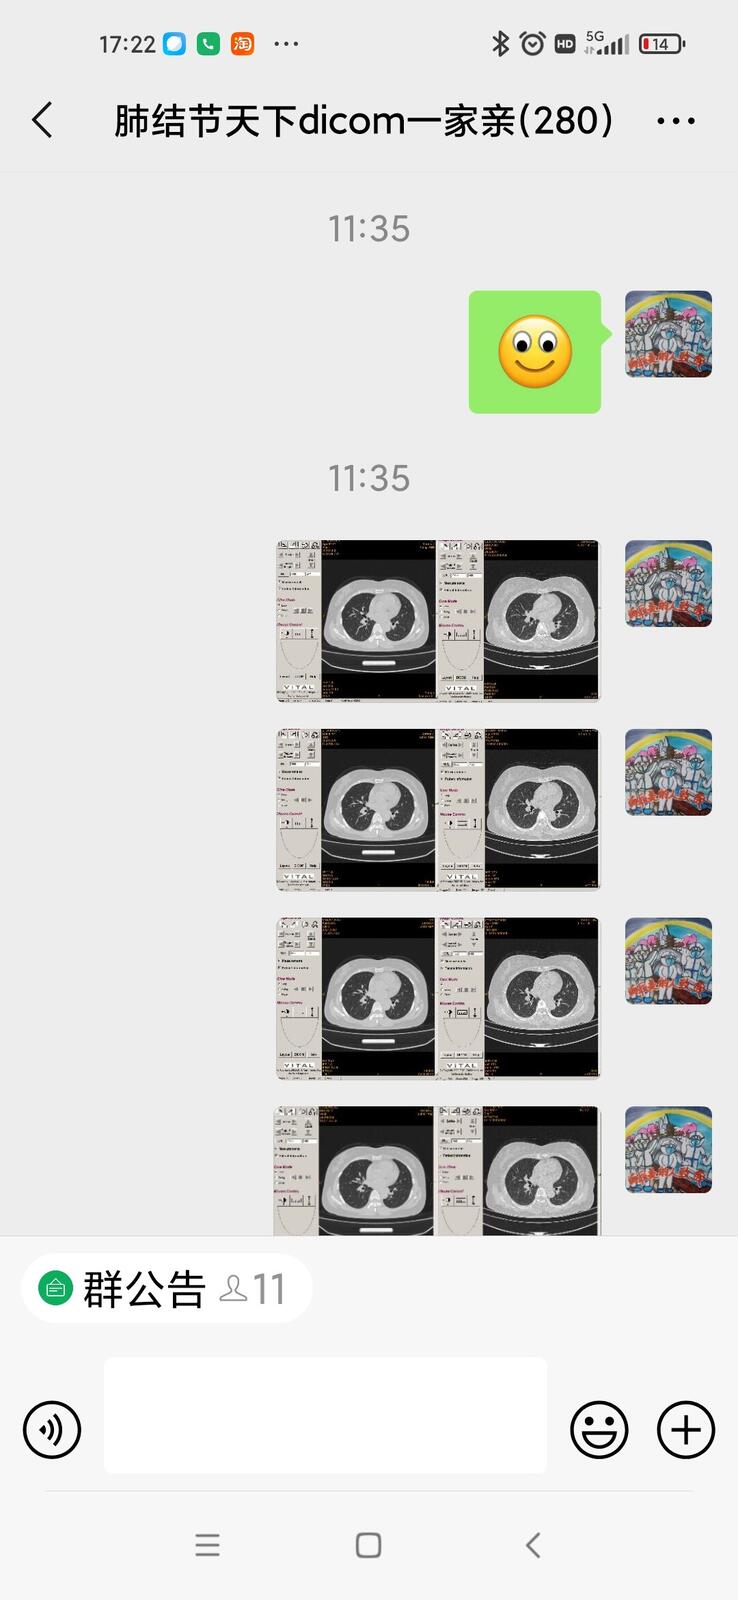

只言片语 之 (7)